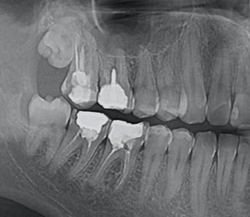

Extinderea tratamentului endodontic la nivelul întregii anatomii este mai sigură în cazul folosirii microscopului operator. În această situație, acestui molar inferior i-au fost tratate 3 canale, așa cum este forma anatomică (Fig. 4.12.1). Doar că în această situație sistemul endodontic prezenta 6 canale, toate instrumentate și obturate cu ocazia retratamentului. (Fig. 4.12.2, Fig. 4.12.3)

În acest caz, pacientul s-a prezentat după un abces acut în antecedente (durere puternică și spontană, cu caracter pulsatil) care a fost tratat cu antibiotice. La analiza imagisticii 3D remarcăm că există o comunicare între materialul din interiorul dintelui și spațiul dintre cele două rădăcini. Se mai evidențiază și material extrudat în acest spațiu, precum și pierdere osoasă. Deducem că este vorba de pierdere osoasă în furcație în urma cimentării unui pivot turnat. Acest pivot a fost cimentat într-un spațiu artificial creat în afara rădăcinii, această acțiune fiind un accident al tratamentului inițial (Fig. 4.12.4). Prima măsură este de a asigura izolarea cu diga dentară. Dintele prezintă o coroană artificială ce trebuie îndepărtată, diga ferește pacientul de contactul cu pulberile rezultate în urma tăierii coroanei (Fig. 4.12.5).